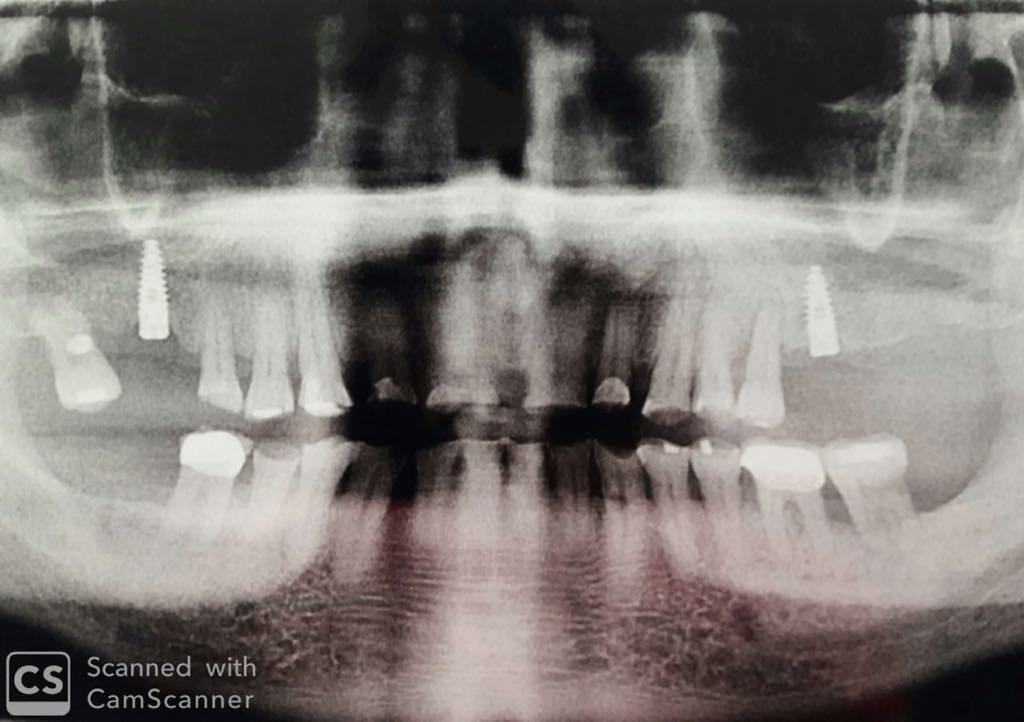

Buenas Tardes, os envío otro de tantos casos que nos llegan a las clínicas con pacientes que no saben lo que llevan puesto en la boca y hace que nos [...]

Paciente de 50 años presenta implante brasileño y se le cambiará corona. Ayuda con que tipo implante es